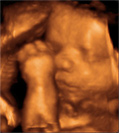

A imagem é tridimensional (3D), mas em vez de congelada como uma foto, o bebê é visto em tempo real, em movimento (4D). Além de agradar a toda a família é possível ver claramente o rosto, mãos e pés do bebê. Realizado entre 26 a 29 semanas.

Para este exame, a paciente não poderá estar em jejum.

Sua carteira pré-natal é seu documento de gestante, tenha sempre em mãos.